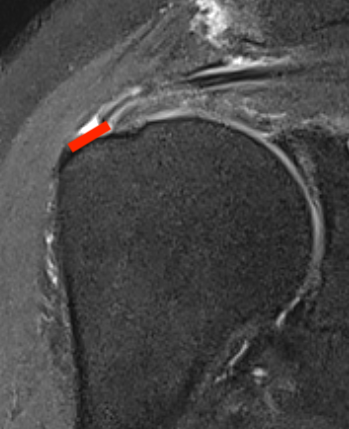

Articular Sided / PASTA (partial articular sided tendon avulsion)

Bursal Sided